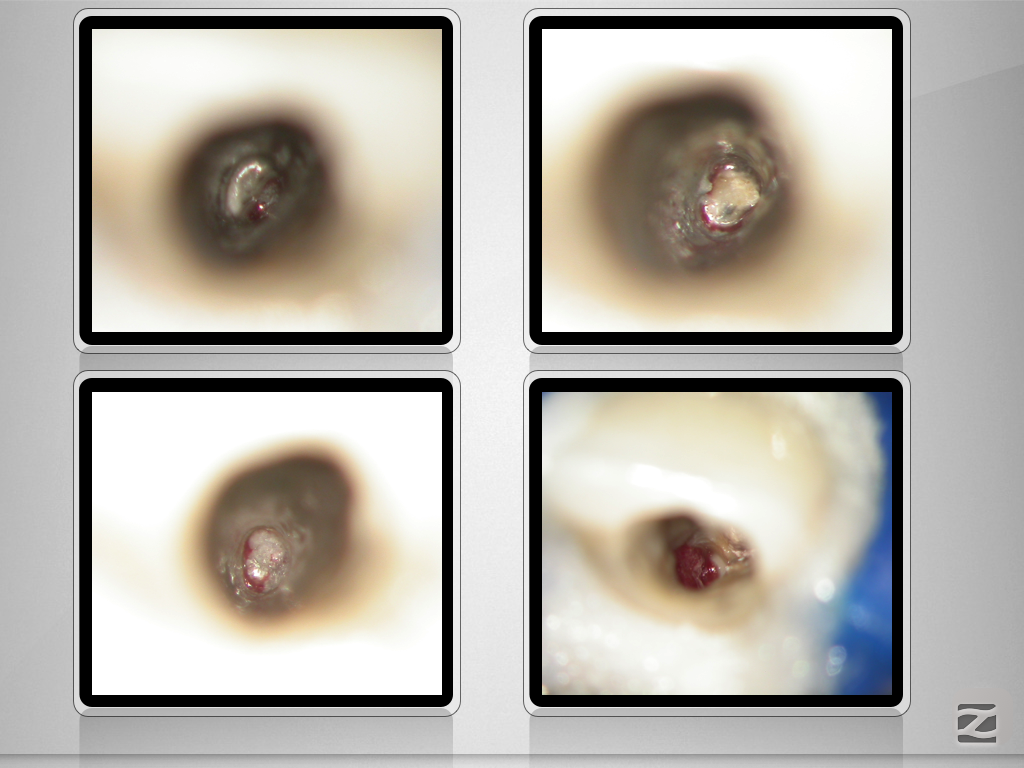

11D.006

An der Grenze …